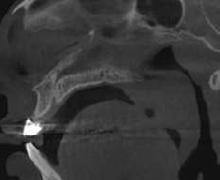

Estudios tomográficos en los cuales se observa tumoración expansiva a piso nasal de 3 centímetros de diá metro aproximadamente isodensa a tejidos blandos en zona de pala dar blando (Figura 3A y 3B). Motivo por el cual se decidió realizar biopsia incisional (Figura 4A , 4B y 4C) obte niendo un diagnóstico de Adenocar cinoma de células basales en paladar blando (Figura 5) con el cual se rea lizó referencia al centro oncológico naval para su seguimiento y trata miento. Actualmente se encuentra en tratamiento de quimioterapia.

Figura 3. Tomografía en corte axial con ventana ósea en la cual se observa paladar duro sin aparente afección ósea. Tomografía en corte sagital con ventana ósea en la cual se observa dimensiones aparentes de la tumoración en paladar blando. A B